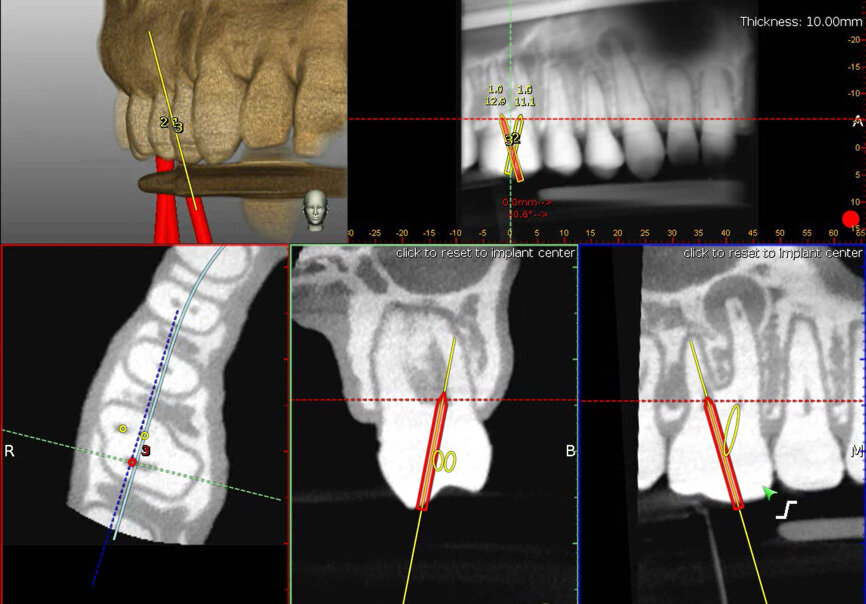

Fig. 4a: The planned axis angulation and orientation of the virtual drill are exacting in targeting calcified canals. (Courtesy of Dr Bobby Nadeau)

Fig. 4b: The red virtual pathway reflects an off-angle positioning. (Courtesy of Dr Bobby Nadeau)

Fig. 4c: Piezotome planning. (Courtesy of Dr Bobby Nadeau)

The first stage of TaP workflow is the importation of the patient’s CBCT data set (as DICOM file) into the dynamic navigation planning software to reveal the dentition. The screen shows the streaming video, panoramic view, target view, depth indicator, and buccolingual and mesiodistal section views (Fig. 3). The access point of entry, the axis orientation/angulation and the depth of the access cavity are planned. For microsurgical procedures, the Piezotome pathway is based on the dimensions of the osseous pathology surrounding the root apex (Figs. 4a–c). The planning stage can be done at any time prior to the procedure, provided the CBCT scan is consistent with the current dentate condition. As a preliminary step prior to the trace registration, three to six trace starting points (landmarks) are chosen and marked on visible and accessible teeth. When the computer mouse is positioned over the 3D model, a 2D cross-sectional view appears. The red crosshair sticks to the landmark, its centre on the surface (Fig. 5). The software advises the clinician if it suspects that the landmark is in an incorrect position.